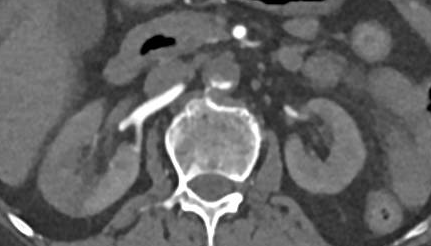

然而在转运途中,患者的胸痛有所缓解,复查心电图显示ST段已开始回落(图2)。因此,王乂医生并未启动“双绕”流程,而是安排患者先进入急诊抢救室进行全面评估。

图2